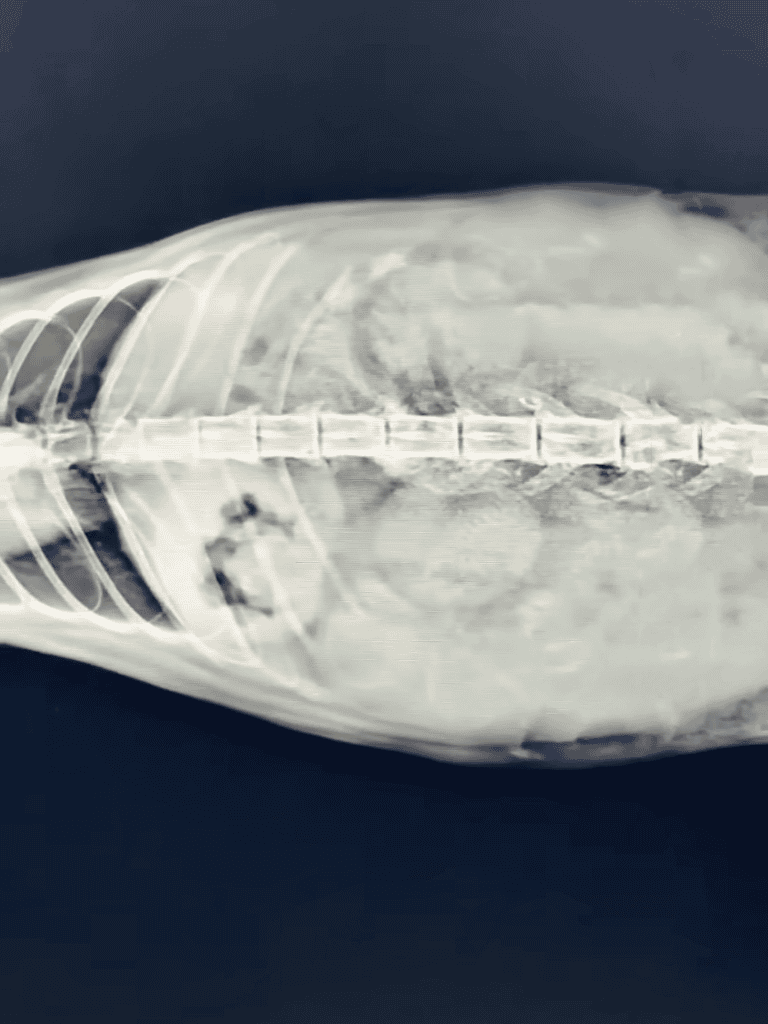

A scan revealed unborn kittens, two of which had weak heartbeats.

Rushing to the hospital, the vet found canine bite marks and discovered the cat was pregnant. Surgery took three hours due to severe injuries.

Once the cat was under anesthesia, the vet began a detailed examination and found evidence of canine bite marks alongside a myriad of old scars etched across her frail body.

A CT scan showed the cat was expecting, with kittens almost ready for their entrance into the world. However,

As the vet examined the fragile kittens, their faint heartbeats echoed the uncertainty of their survival. A race against time began, with immediate surgery standing as the only hope to save their fragile lives.

The anticipated one-hour surgery turned into a grueling three-hour ordeal due to the cat’s extensive injuries.

They rushed to a vet, where examinations found not just canine bites but near-term kittens.